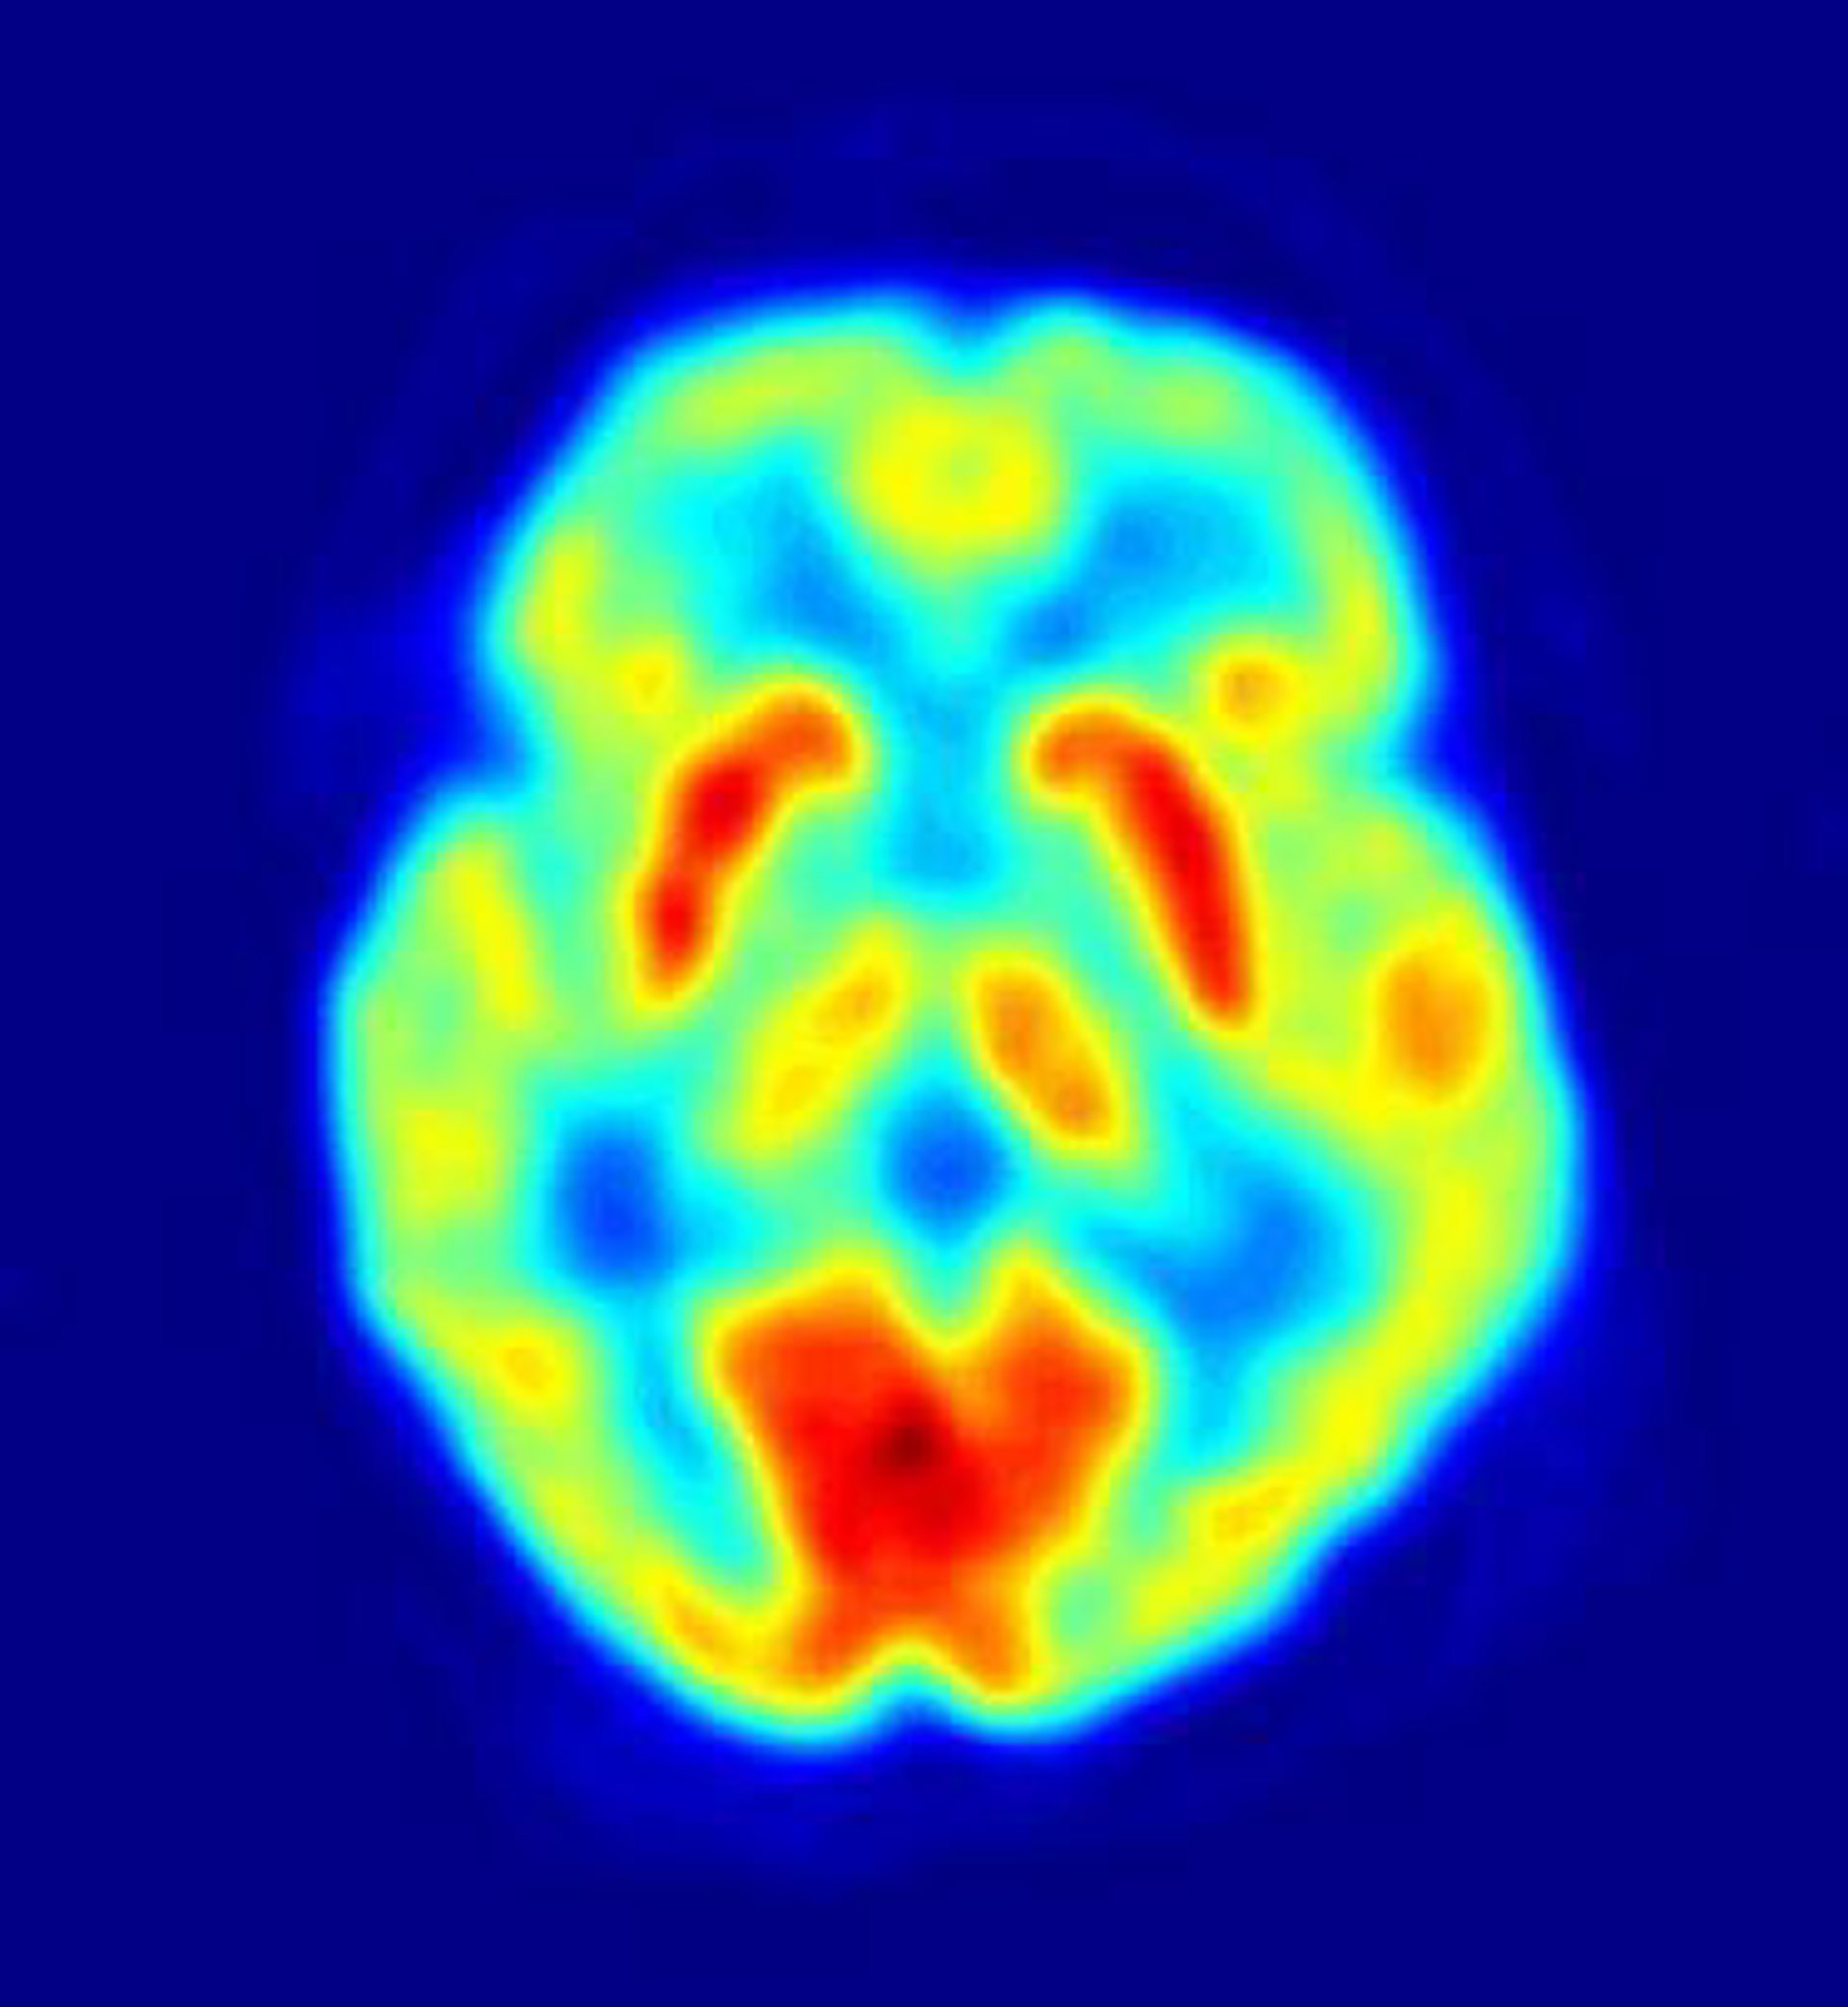

El cerebro procesa las 'recompensas', como comida, dinero o música agradable, que crean respuestas positivas en el organismo, en áreas como la corteza ventromedial prefrontal (CVMPF) y el estriado ventral.

En sus experimentos, los investigadores examinaron cómo el CVMPF y el estriado ventral reaccionaban en 40 voluntarios a los que se les presentaba una serie de escenarios de transferencia de dinero mientras pasaban por un escáner de imágenes de resonancia magnética funcional (IRMf).

Así, en uno de los casos al participante se le decía que se le darían 50 dólares y 20 a otra persona; en un segundo escenario, el estudiante podía ganar sólo 5 dólares y la otra persona 50. Las imágenes de IRMf permitían a los investigadores examinar cómo el cerebro de cada participante respondía a cada posible intercambio económico.